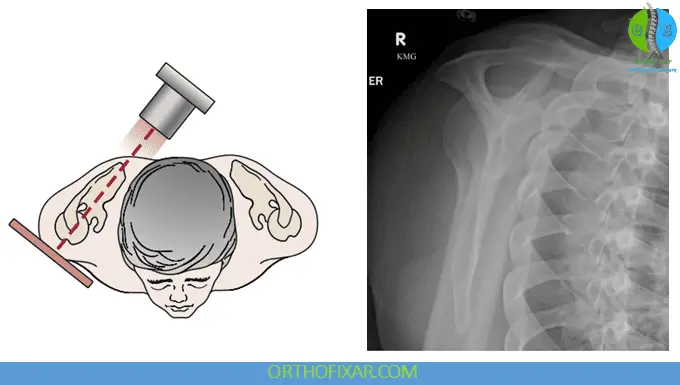

Trans-scapular (Y) Lateral (Outlet) View

The trans-scapular lateral view, also known as the Y view or outlet view, represents the true lateral projection of the scapula. This view is invaluable for assessing the position of the humerus relative to the glenoid and evaluating the morphology of both the acromion and coracoid processes.

Clinical Significance

The outlet view is used to determine the coracoacromial outlet shape and its contribution to impingement syndrome. By visualizing the subacromial space from a lateral perspective, clinicians can better understand the mechanical factors contributing to rotator cuff pathology.